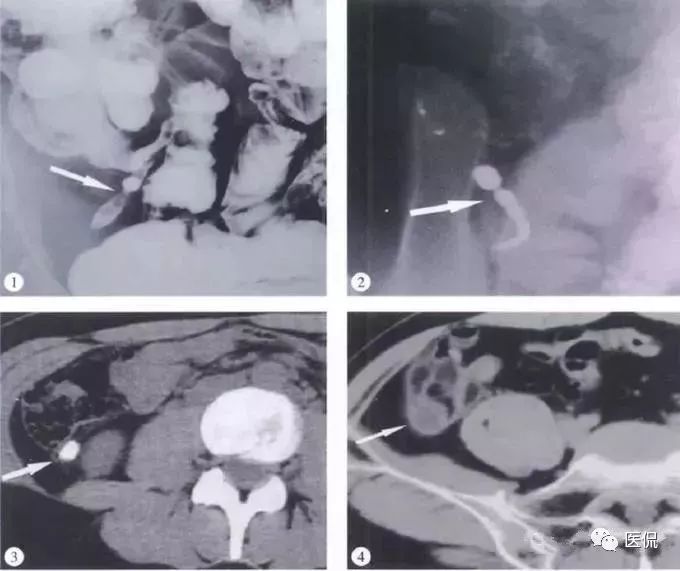

(1)BE:盲肠内侧壁光滑球形肿块压迹,末端小肠推压移位。阑尾未见钡剂充盈。

(2)右下腹卵圆形肿块,有或无钙化声影。腔内以低度回声典型。

(3)CT:盲肠尖区域薄壁囊性肿块,边界清晰,呈长圆形,与盲肠间解剖关系密切,环形钙化壁。增强壁强化,内容物无强化。腔内出现气泡/气液平伴感染。腹膜假黏液瘤典型为腹膜分叶病变,使空腔脏器移位或变形,实质器官边缘呈“扇贝”改变。

(4)MRI:右下腹囊性肿块,冠状面位髂肌和腰大肌形成“V”形间隙内,与盲肠关系密切,可位于盲肠内下方或后下方,盲肠外压改变。